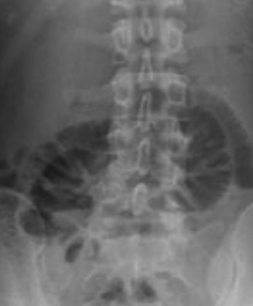

Plain abdominal radiograph. Nonspecific findings of intestinal obstruction (Courtesy Dr. V. Penopoulos)

Red arrows — transition point. Multiple air-fluid levels (Courtesy Dr. V. Penopoulos)